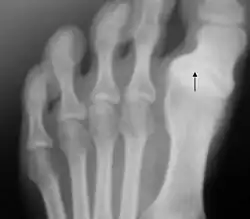

Entre las afecciones infecciosas destaca la osteomielitis crónica del sesamoideo. Esta infección tiene lugar por ulceración o introducción de un objeto extraño. Uno de los agentes patógenos implicados suele ser Pseudomonas.[23] La sesamoiditis es una patología asociada a la inflamación de los huesos sesamoideos que se encuentran en la articulación metatarsofalángica, y produce un dolor característico en la base del dedo gordo por la cara plantar.[86]

Un traumatismo frecuente en jugadores de rugby y otros deportes es el esguince de la articulación metatarsofalángica, también conocido como dedo del césped o del turf. Se suele producir por hiperdorsiflexión de la articulación. La clasificación de Jahss describe los diversos grados de luxación de esta articulación, y la clasificación de Clanton el grado de severidad del esguince.[23] En el fútbol son frecuentes los traumatismos en el dedo gordo del pie, que se producen cuando el pie del jugador está en posición pronada y con el talón al aire.[39] La enfermedad de Renander es una osteocondrosis que afecta a los sesamoideos, más frecuentemente en mujeres de entre 9 y 17 años, y que se produce por microtraumatismos deportivos.[87]